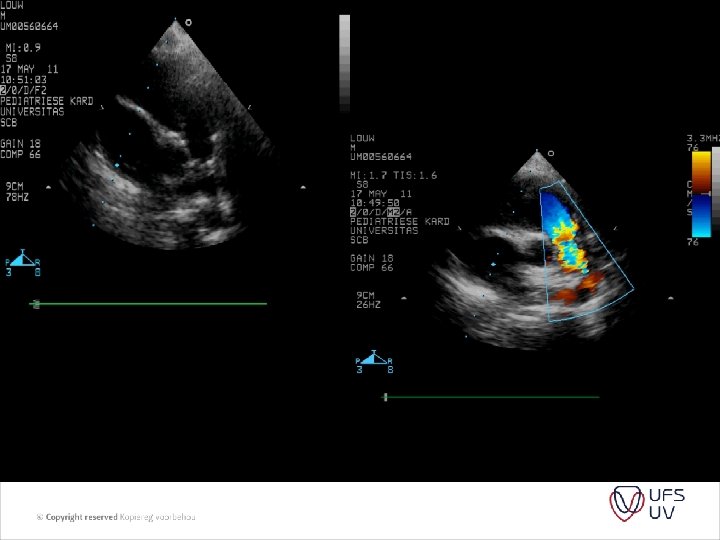

DIAGNOSIS • Clinical - AP, Load P 2 , RVHT, HTS • ECG/CXR - RVHT , p-pulmonale, decreased flow, RVHT, PA • Echo - usually indirect - variable - patient / songrapher / machine dependant - RVPSP - needs TR - PIG – needs shunt - BP - can be inacurate

PVR = PAP/ PAflow Substitude PA pressure with TR jet Substitude PA flow by RVOT VTI (velosity time integral) And we get PVR = TR jet velocity/ RVOT VTI x 10

• • Figure 1 Images showing peak tricuspid regurgitant velocity (TRV) and right ventricular outflow time-velocity integral (TVIRVOT) in a patient with normal pulmonary vascular resistance (PVR). (A) TRV is 2. 86 m/s. (B) TVIRVOT is 20. 8 cm. The ratio of TRV/TVIRVOT = 2. 86/20. 8 = 0. 1375. . This patient’s invasive PVR measurement was within 0. 4 WU of the echocardiographic value (PVRCATH = 1. 3 WU). PVRECHO = PVR in WU calculated based on the linear regression equation in which a value for PVR in WU was modeled based on TRV/TVIRVOT. PVRCATH = invasive PVR.

• Figure 2 Images showing TRV and TVIRVOT in a patient with elevated PVR. (A) TRV is 3. 64 m/s. (B) TVIRVOT shows a clear deceleration of pulmonary flow before the pulmonic valve closure click and is calculated at 6. 5 cm. The ratio of TRV/TVIRVOT = 3. 64/6. 5 = 0. 56. . This patient’s invasive PVR measurement is also within 0. 4 WU of the echocardiographic value (PVRCATH = 6. 0 WU). Abbreviations as in Figure 1. • • J Am Coll Cardiol, 2003; 41: 10211027